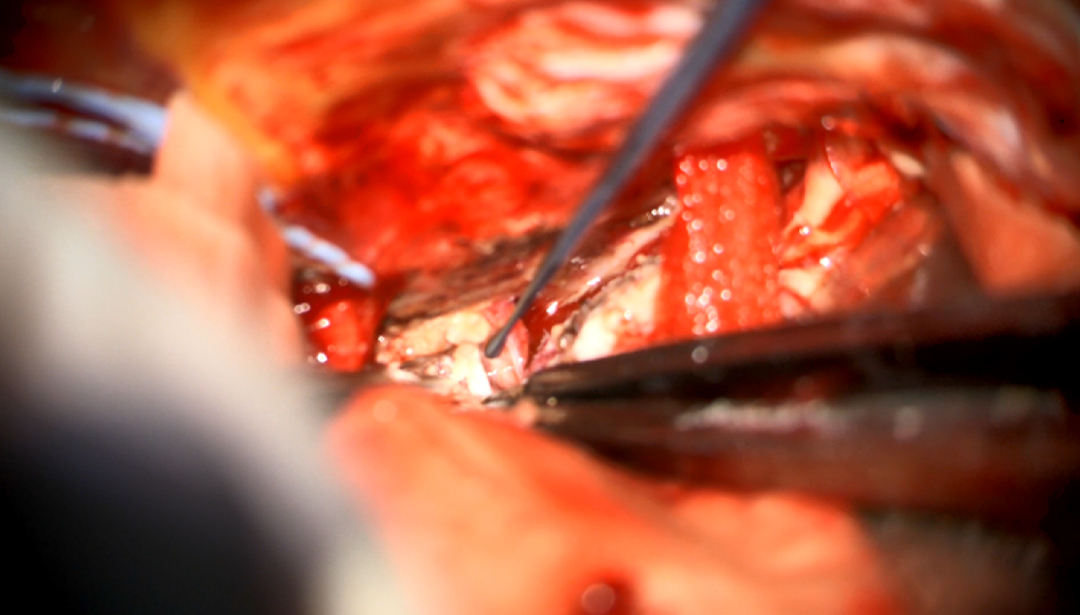

术中图片:

图10. 显露肿瘤

图11. 松解齿状韧带,进一步暴露肿瘤

图12. 分块切除肿瘤

图13. 处理肿瘤基底

14. 暴露肿瘤上极

图15. 暴露肿瘤下极

图16. 肿瘤全切

图17. 硬脊膜水密缝合